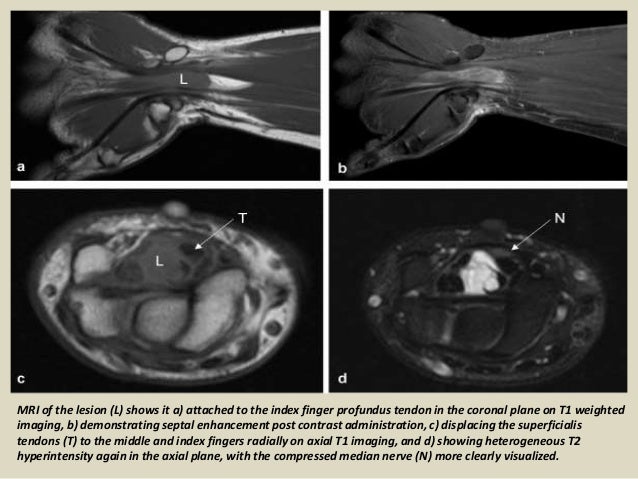

Carpal tunnel syndrome (cts) is a collection of symptoms and signs caused by compression of the median nerve in the carpal tunnel at the wrist.